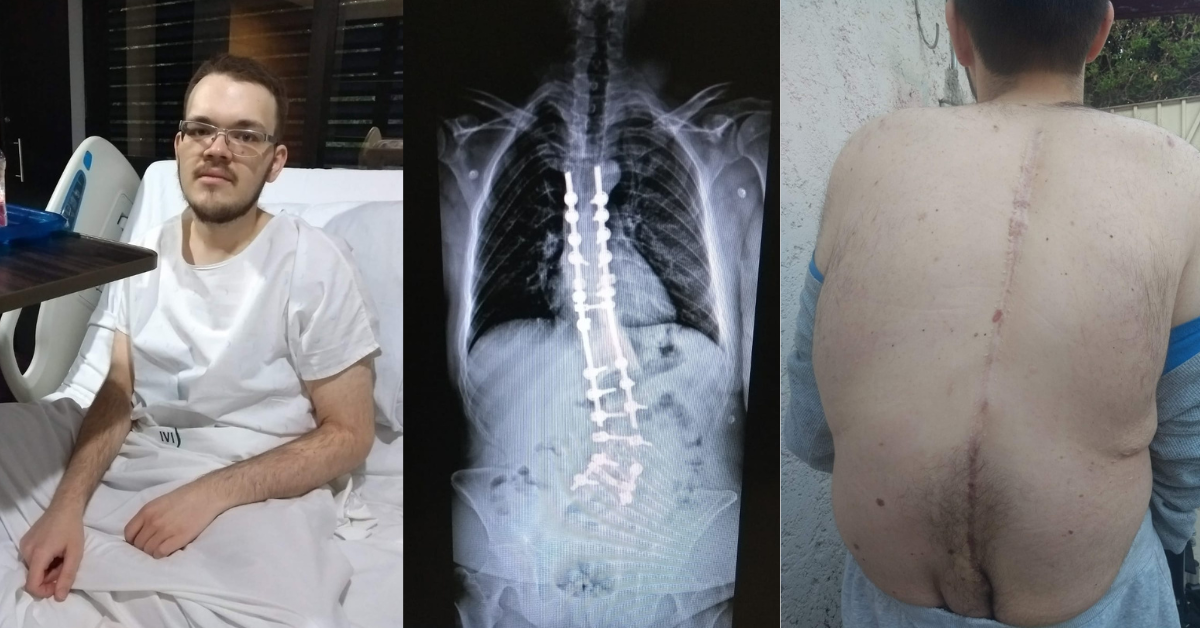

Christopher nació con escoliosis congénita, una malformación en la columna que desde la adolescencia le provoca dolor crónico e incapacitante. A los 14 años fue sometido a una cirugía en la que le colocaron barras de titanio para enderezar su columna. Aunque la operación parecía exitosa, el dolor nunca desapareció debido a daño nervioso y a su proceso de crecimiento.

Christopher was born with congenital scoliosis, a spinal malformation that has caused him severe, chronic pain since adolescence. At 14, he underwent surgery in which titanium rods were implanted to straighten his spine. Although the surgery appeared successful, the pain never subsided due to nerve damage and continued growth.